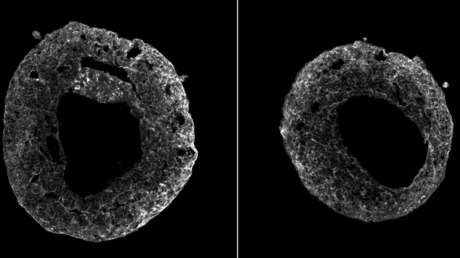

Un modelo de corazón fue cultivado en la Academia de Ciencias de Austria con base en células madre humanas, publica la revista Cell. Asimismo, los científicos divulgaron el video del latido del órgano, del tamaño de un grano de sésamo.

Para simular la autoorganización del corazón, Mendjan y sus colegas activaron seis vías de señalización involucradas en el desarrollo del órgano en embriones. Tras una semana de crecimiento, las células crearon una estructura 3D con una cavidad cerrada, repitiendo la trayectoria del desarrollo del corazón en un embrión. Asimismo, detectaron contracciones rítmicas del órgano.